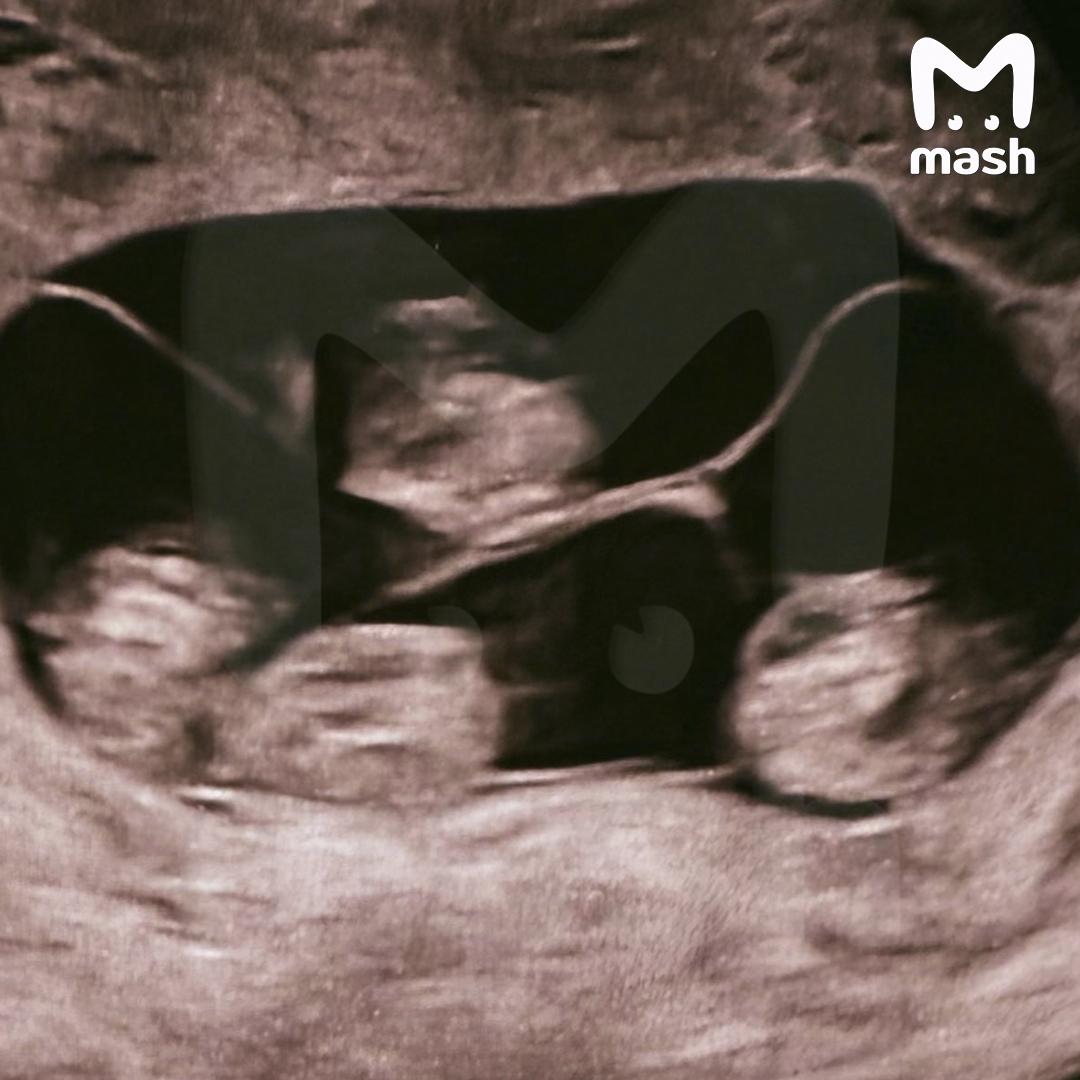

Впервые в России женщина родила однояйцевую четверню — такое происходит 1 раз в 15,5 миллиона родов. Все четверо — неотличимые девочки-близнецы.

По нашей информации, вес новорожденных малышек из Петербурга от 1360 до 1640 граммов, а рост — от 37 до 41 см. Сейчас они находятся под наблюдением врачей.

Всего в мире насчитывается около 15 идентичных четверняшек, причём 10 из них — девочки.